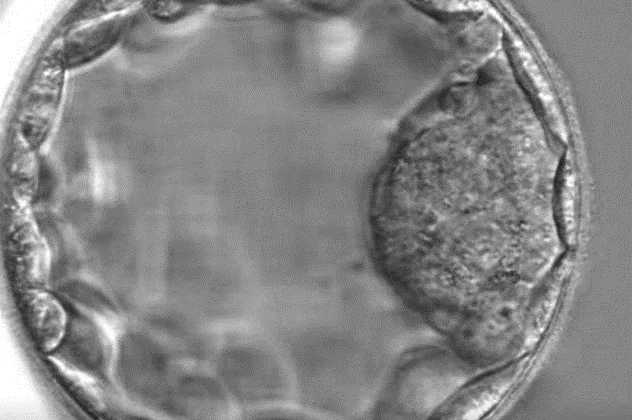

Blastocist: Embrion de cinci zile

Blastocistul este un stadiu timpuriu de dezvoltare a embrionului care apare în ziua a cincea după fertilizare. Celulele blastocistului sunt împărțite într-un strat interior, embrioblastul, care mai târziu formează fătul, și un înveliș exterior, trofoblastul, care dă naștere placentei.

În acest stadiu, embrionul este, de obicei, transferat în uter, iar calitatea blastocistului determină dacă va fi sau nu potrivit pentru transfer.